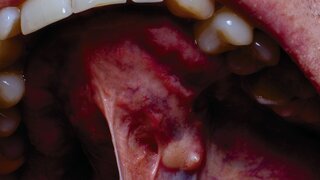

US-Studie zu Per- und PolyfluoralkylsubstanzenEwige Chemikalien im Trinkwasser erhöhen das Mundkrebsrisiko Per- und Polyfluoralkylsubstanzen (PFAS) im Trinkwasser erhöhen laut einer US-Studie das Risiko von Krebs in den Bereichen Verdauung, Endokrinologie, Mundhöhle/Rachen und Atemwegen um bis zu 33 Prozent. Ausgabe 3/2025Medizin